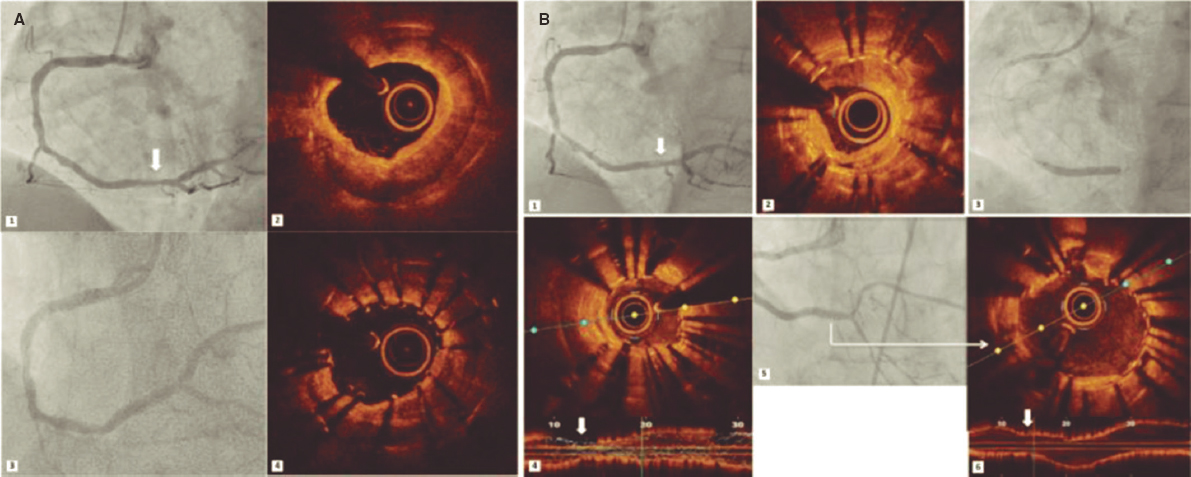

CASE PRESENTATION

This is the case of a 51-year old male without a past medical history. One month before his admission he experienced fast heart palpitations associated with diaphoresis, nausea and vomit. Both the electrocardiogram and the Holter monitor showed recurring episodes of monomorphic ventricular tachycardia (figure 1). The physical examination confirmed the presence of an aortic ejection murmur exacerbated when performing the Valsalva maneuver. The transthoracic echocardiography showed obstructive asymmetric septal hypertrophy with a 32-mm maximum septal diameter (figure 2A), a 65-mmHg gradient in the left ventricular outflow tract, and systolic anterior motion of the mitral valve with moderate regurgitation. The cardiovascular magnetic resonance imaging confirmed the presence of extensive myocardial fibrosis as a risk factor of sudden death (figure 2B and video 1 of the supplementary data). Amiodarone and propranolol were prescribed, and an automatic defibrillator was implanted as a secondary prevention measure. The patient was readmitted to the hospital 4 months later with signs of electrical storm with multiple discharges provided by the device implanted. Deep sedation, mechanical ventilation, and hemodynamic support were administered, and the stellate ganglion was blocked. However, the patient progression was poor with persistent episodes of ventricular tachycardia that triggered the mapping of cardiac electrophysiology using the CARTO 3 system (Biosense Webster, Israel). The ablation of a septal macroreentrant circuit of the left ventricle associated with the clinical ventricular tachycardia was unsuccessful (figure 2C).

A bail-out alcohol septal ablation procedure was attempted that showed a 65-mmHg intraventricular gradient. After the 110-mmHg extrasystole bubble contrast was injected to choose the target septal branch (figure 3) followed by the injection of 0.1 mL of alcohol per millimeter of contrasted septum. In the echocardiography a 23 mm contrasted septum was measured, and 2.3 mL of alcohol were administered in the second septal branch.

Figure 3. A: coronary angiography. B: injection of bubble contrast in the second septal branch. C: contrast enhancement of the susceptible septal region (arrow). D: over-the-wire balloon used for the administration of alcohol.